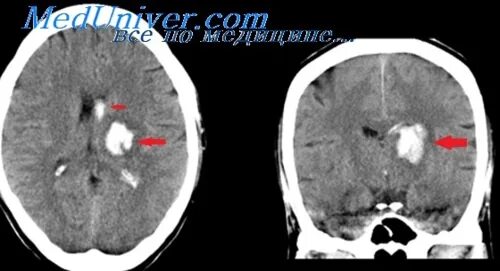

Отек мозга ишемия